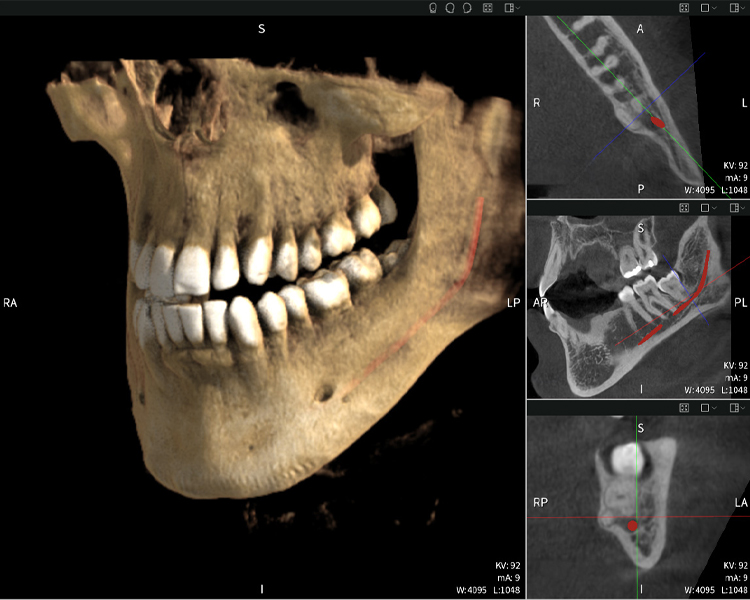

Abbildungen b–d zeigen verschiedene Ansichten einer 3D-Rekonstruktion des Unterkiefers und bieten eine umfassende Übersicht über die Anatomie des Unterkiefers, die Lage der Nerven im Verhältnis zu den Zähnen und ermöglichen die Beurteilung der Zahnsymmetrie und Ausrichtung.

Abbildung d zeigt den bereits vorbehandelten Zahn 48, dessen Krone entfernt wurde und dessen Wurzeln nahe am Nerv belassen wurden, was das hohe Risiko einer Nervenschädigung verdeutlicht.